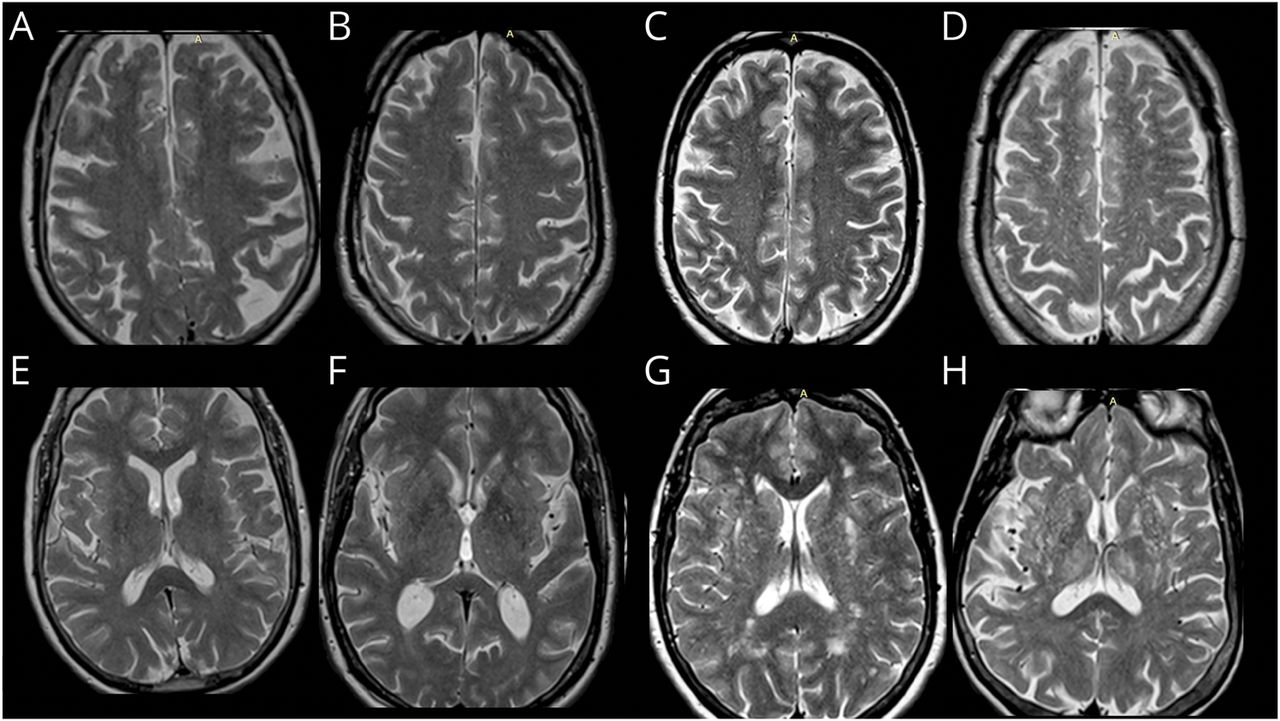

核磁共振扫描被评为3经验丰富的调查人员(neuroradiologist、血管神经学家和一个训练有素的研究助理)的受试者的人口统计学、临床和结果信息。当可用时,pv评级进行轴向核磁共振t2加权序列使用验证方法,根据他们的大脑pv地形分成中枢semiovale(方案)和基底神经节(BG)。15pv的负担是分为成绩基于pv数:我(1 - 10),二(11日至20日),3(- 40),和第四(> 40)。一个代表性的例子所示图2。

行椎体上部semiovale: (A)年级我(1 - 10 pv数),(B)二级(11日至20日pv数),(C)三级(意向pv数)和(D)年级第四(> 40 pv数)。底下一行基底神经节区:我(E)年级(1 - 10 pv数),(F)二级(11日至20日pv数),(G)三级(意向pv数)和(H)等级IV (> 40 pv数)。pv =血管周的空间,FHS =弗雷明汉心脏研究。